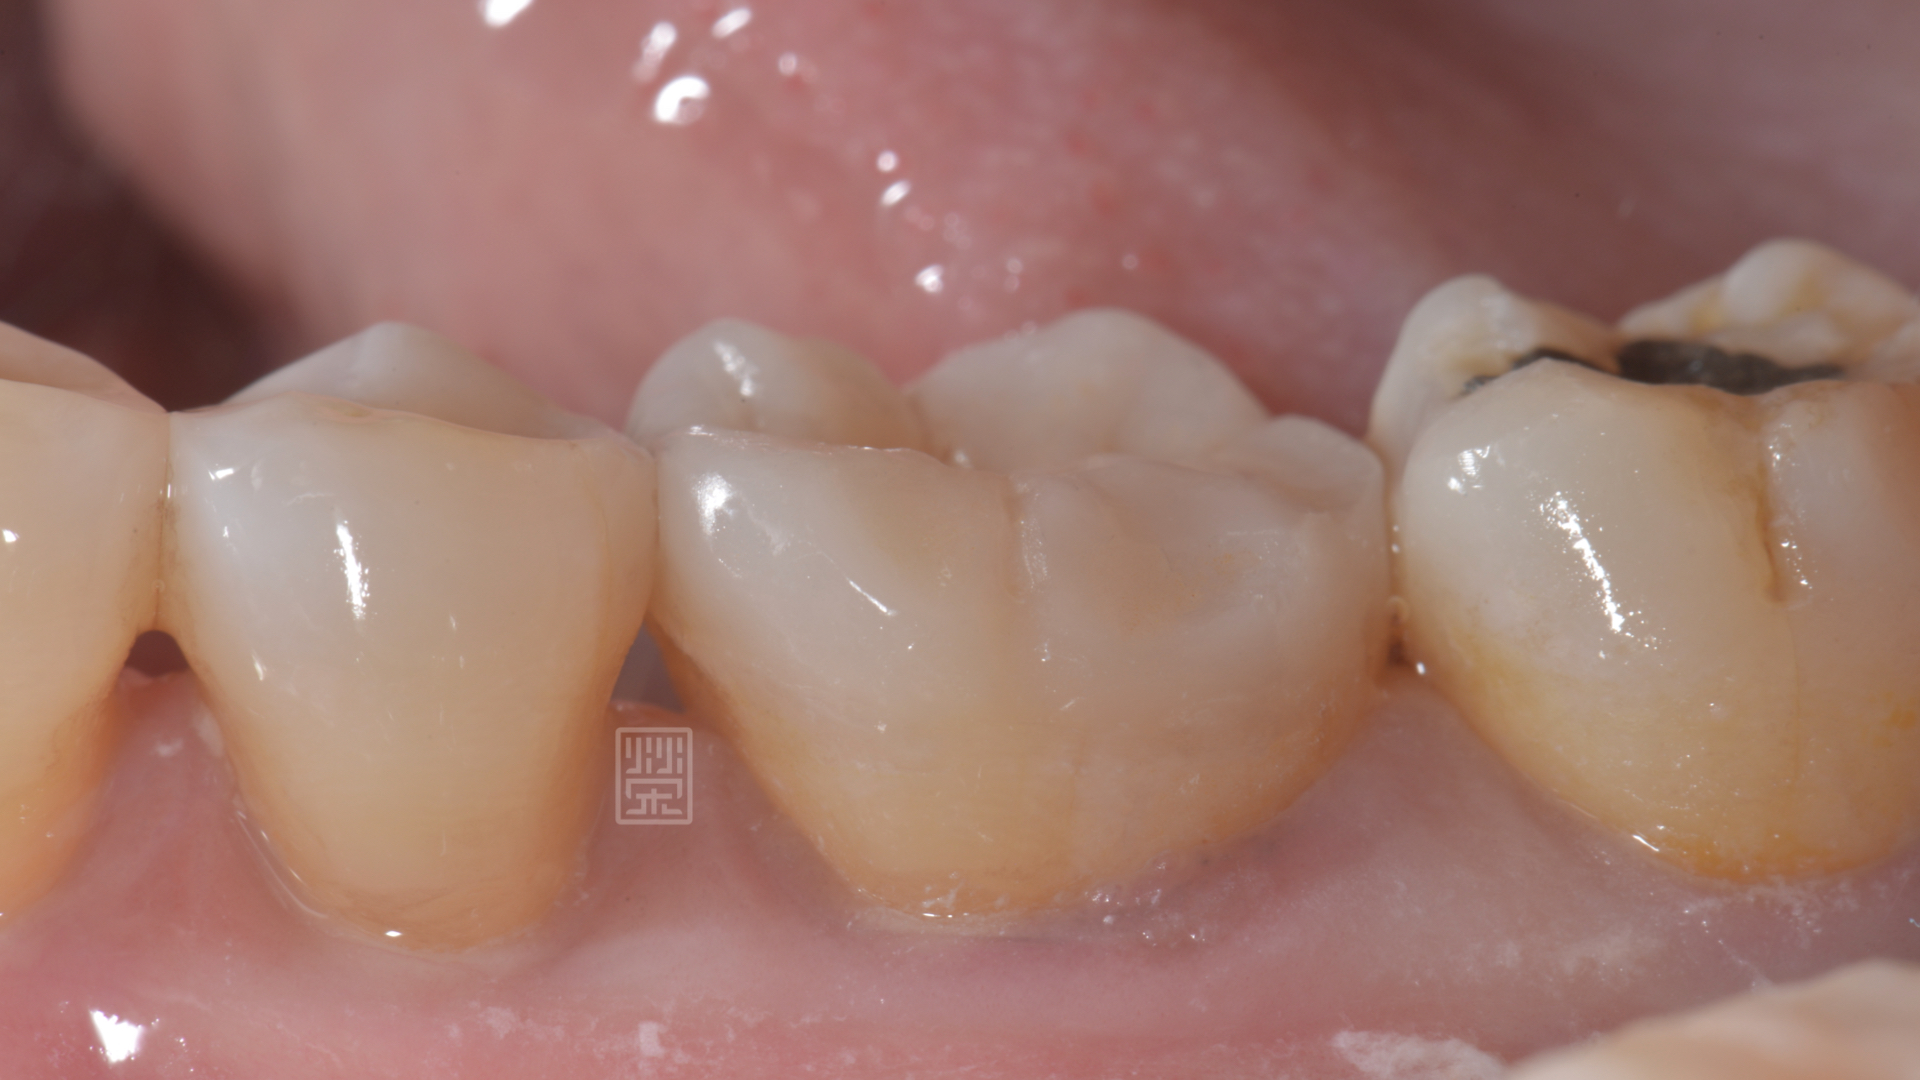

楊女士因為上顎第二大臼齒缺牙,所以咬合重心都是在第一大臼齒咬合對,前陣子突然發覺咬東西有點痛痛的,以為是牙齦發炎,認真刷牙後,狀況並未改善,來榮醫師診間就診,發現除了咬合面明顯磨耗,牙本質都裸露之外,頰側面有明顯的縱向裂痕,還好的是牙齒神經並未造成不可逆傷害,建議製作全瓷嵌體,將牙齒戴上保護罩,減少治療過程牙齒的傷害。

咬合面耗損